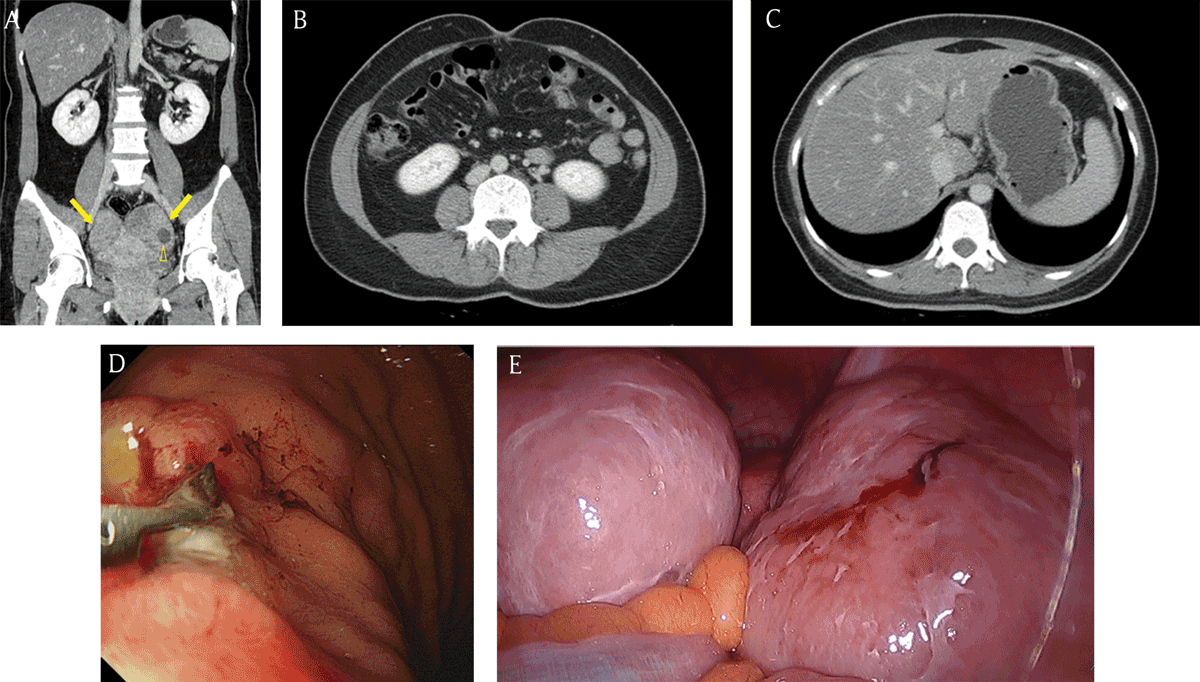

Figure 4

A 40-year-old woman with incidentally detected bilateral ovarian masses. (A) Coronal reformatted contrast-enhanced CT image demonstrated the heterogeneous enhancing masses (arrows) in the bilateral ovaries. Note the small cystic component (open arrowhead) within the ovarian mass. (B, C) There was no evidence of ascites, peritoneal thickening, abnormal lymph nodes, or a malignant tumor within an intra-abdominal solid organ or the gastrointestinal tract on the CT image. (D) Gastric adenocarcinoma with signet ring cell component was confirmed by endoscopy. (E) After surgical resection, the masses were diagnosed as Krukenberg tumors. Other peritoneal seeding lesions were detected in the surgical field.